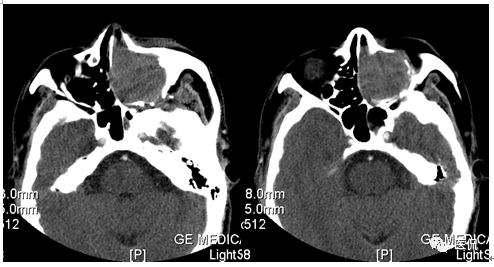

增强水平位FST1WI

CT平扫及增强示:左侧上颌窦及鼻腔可见软组织密度影,呈膨胀性生长,周围骨质压迫性吸收破坏,累及左眶,病灶密度不均匀,周边区可见点状钙化,增动脉期轻度强化,局部见小灶性稍高密度区,静脉期病灶内见不均匀明显强化,CT值最高达117HU,延迟期强化范围有所增大。

影像学表现呈软组织密度,多不均匀,表现为高低混杂密度,病变窦腔内息肉、血肿、坏死、感染共存,是病灶密度不均匀的主要原因,息肉反复出血、血管机化亦为其成因之一。病灶内钙化,可为团块状或小片状,可能为病变组织坏死后钙质沉着所致。由于病变组织内有大量炎性细胞浸润和丰富的毛细血管,增强后常有强化。有文献报道病灶增强中心区强化不明显,外周呈轻度强化,推测病灶内虽然血管丰富,但中心区容易出现血流动力学障碍,血管内常有血栓形成,中心区易发生出血坏死,另外,可能与增强扫描延迟时间选择不当有关。

本例病灶较大,周围骨质可见吸收破坏,并累及眼眶,病灶内少量钙化,增强扫描具有一定特征性,表现为动脉期轻度强化,局部见小灶性稍高密度区,静脉期病灶局部呈明显强化,CT值最高达117HU,延迟期强化范围有所增大,呈延迟渐进性强化的特点,推测为病灶内出血所致。